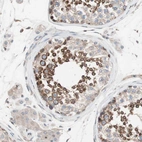

Immunohistochemical staining of human Prostate shows strong cytoplasmic positivity in glandular cells.